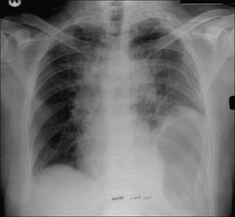

image

Figure 32.15 Male. Age 23. RTA. Left-sided rib fractures (note that a flail segment is present). Pneumothorax. The consolidation in the left upper lobe is an area of lung contusion.